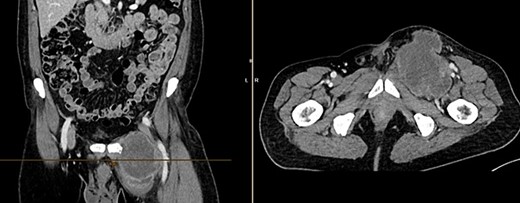

A month later, the patient presented again as the mass in the left groin area had increased in size. A CT (Fig 4) and another excision biopsy were performed. Histological examination revealed parts of a pleomorphic, most likely mesenchymally differentiated neoplasm. It was determined that the presence of a metastasis of the known prostate carcinoma could be ruled out. A myxofibrosarcoma was considered as a differential diagnosis, although the proliferation rate was rather low for this. Therefore, a reference pathology review was initiated.

CT of the abdomen from 26 July 2023: size-progressive metastasis in the left groin with infiltration of the adductor muscles; no dynamics in the primarily osteoplastic diffuse osseous metastasis.